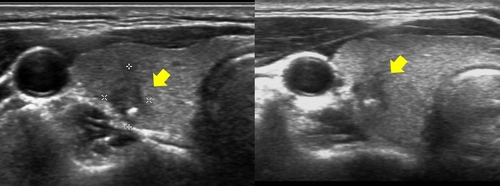

갑상선암 증상 - 5. 결절

대부분의 갑상선암은 목 앞쪽 목젖 아래에서 느껴지는 통증이 없는 결절로 시작됩니다. 따라서이 결절은 일반적으로 샤워로 목을 씻거나 건강 검진 중에 발견 될 수 있습니다. 그리고 모든 결절이 암인 것은 아니지만 양성과 악성으로 나뉘며 대부분은 양성입니다. 또한 60 세 이상 30 세 미만의 사람들에게서 발생하는 결절은 악성 일 가능성이 더 높습니다.

갑상선암 증상 - 8. 목에 혹

갑상선암은 통증이 없기 때문에 초기에 발견하기 가장 어려운 질병 중 하나이지만, 갑상선 결절을 자가 진단하는 한 가지 방법은 목을 부드럽게 마사지하여 만져지는 혹이 있는지 확인하는 것으로, 식도 쇄골에서 시작하여 턱 밑으로 내려온 다음 목 뒤의 승모근에서 시작하여 목 뒤쪽으로 올라가면서 만져지는 혹이 있는지 확인할 수 있습니다.